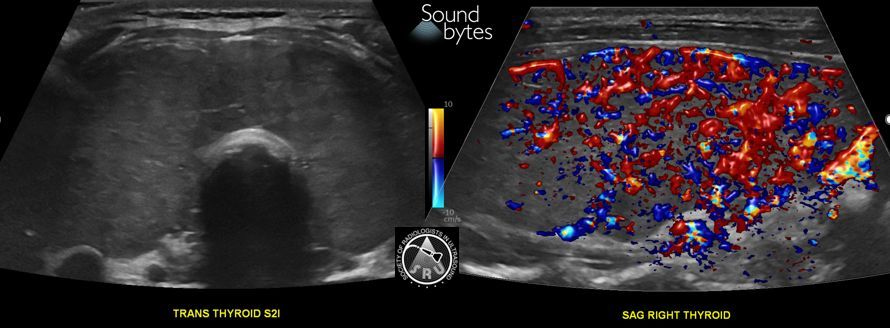

@sruradiology

SRU Radiology

2 months

Patient with fever and confusion. What's your sound diagnosis? Case Courtesy of Naiim Ali, MD, University of VT #RadInTraining #RadRes #ultrasound